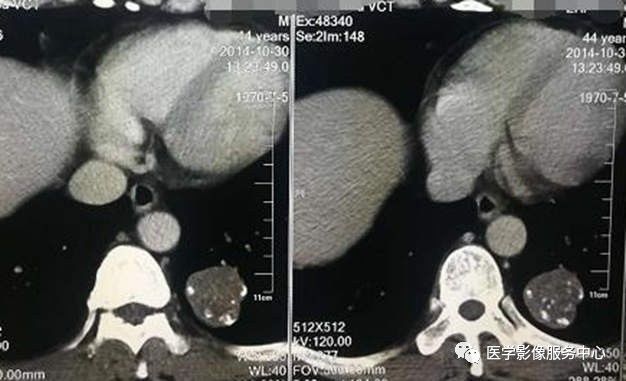

胸部CT平扫

胸部CT增强

CT表现:左肺下叶不规则肿块影,内见脂肪密度及多发钙化,增强扫描未见明显强化,纵隔未见肿大淋巴结。

CT:病灶边缘光滑,圆形或者类圆形,可有分叶征,其内多有脂肪密度及斑点状钙化,典型钙化为爆米花样钙化,增强后肿块无强化或仅轻度强化。